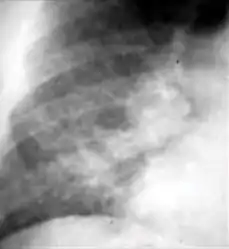

Tuberculosis creates cavities visible in x-rays like this one in the patient's right upper lobe.

2. Any cavitary lesion - Lucency (darkened area) within the lung parenchyma, with or without irregular margins that might be surrounded by an area of airspace consolidation or infiltrates, or by nodular or fibrotic (reticular) densities, or both. The walls surrounding the lucent area can be thick or thin. Calcification can exist around a cavity.